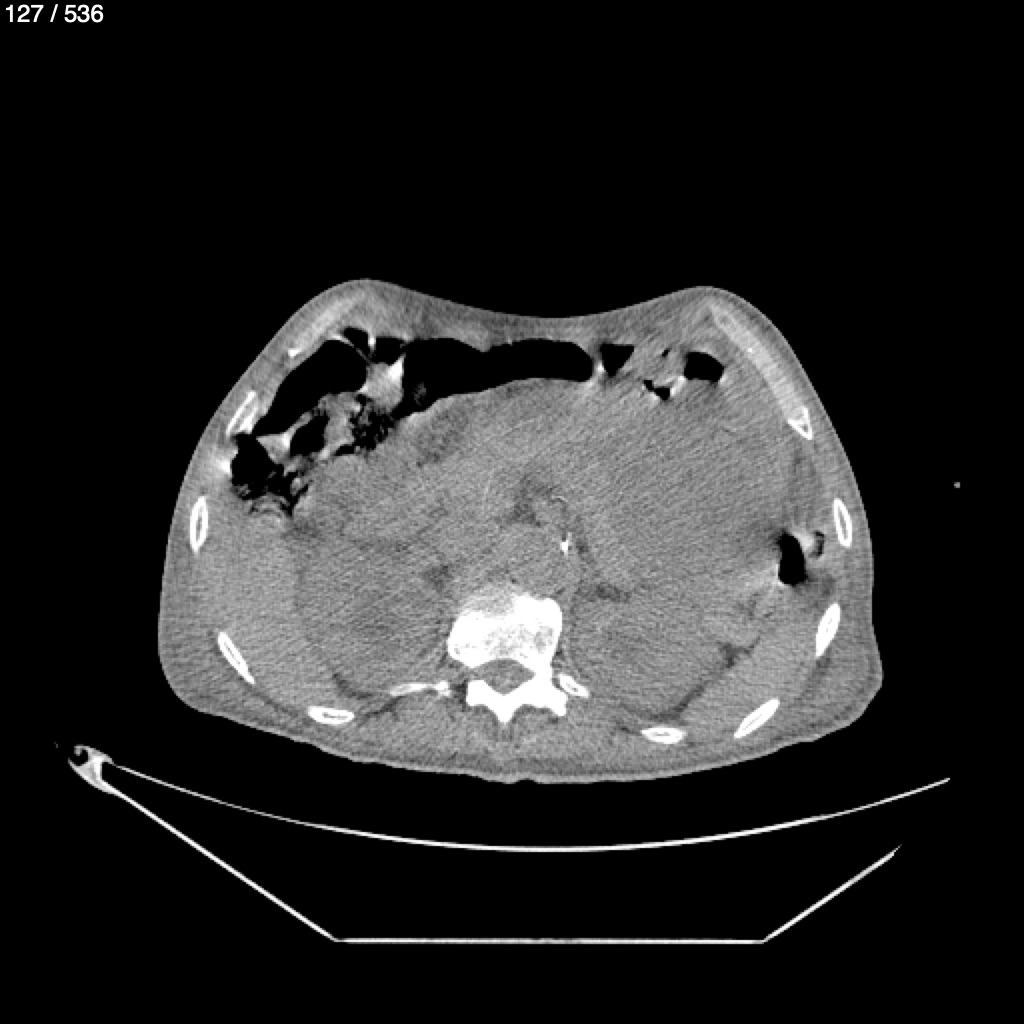

Angel Villalobos Palomeque 73 A - T.C Abdomen Simple